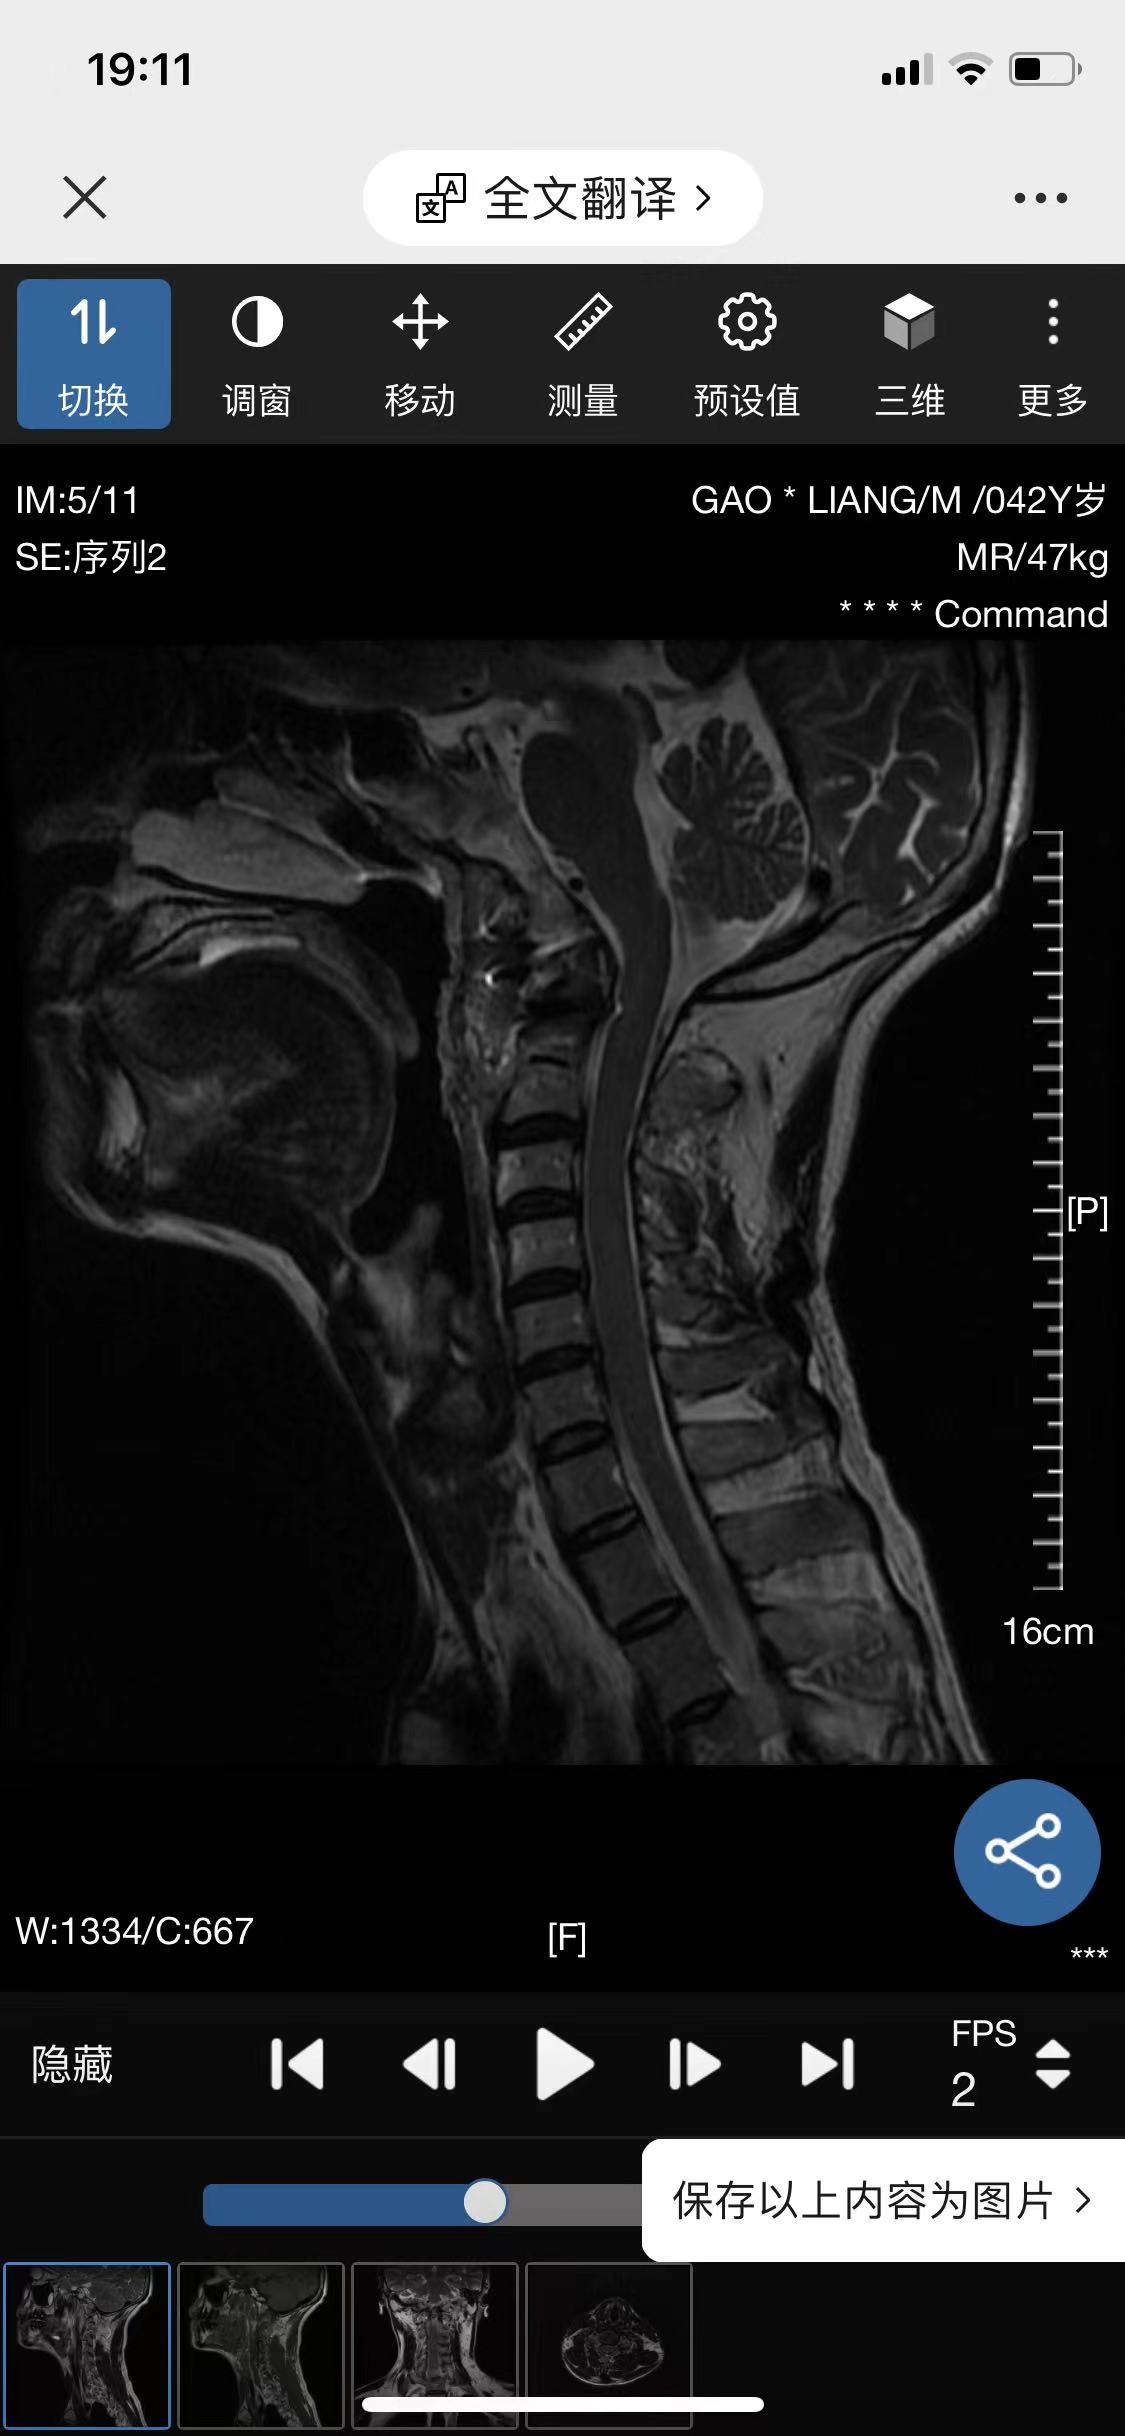

• 诊断:寰枢椎脱位

• 影像: